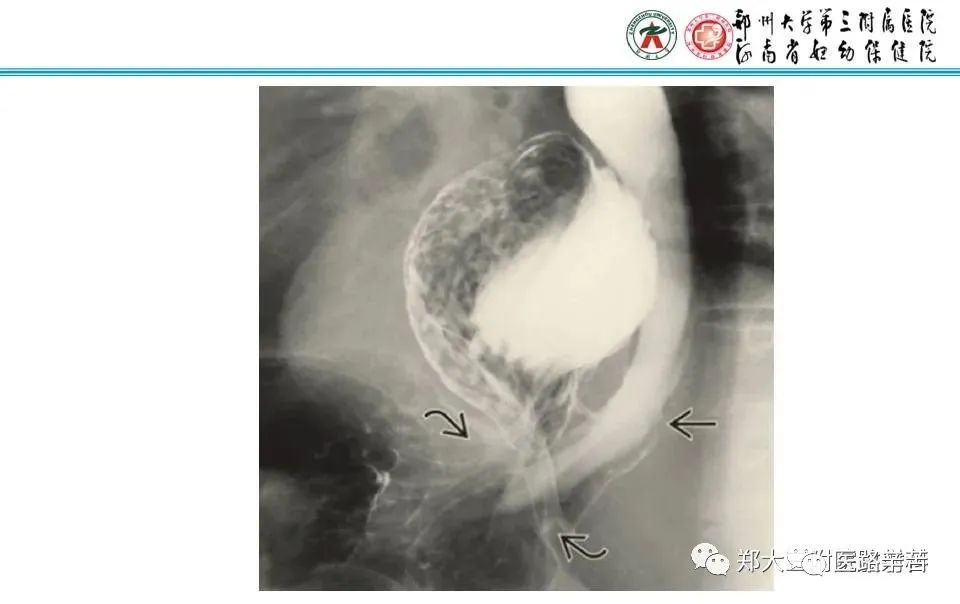

二、Morgagni疝(胸骨旁疝)

胸骨旁疝相对少见,约占膈疝的3%,疝容物多为横结肠。一般无明显症状,偶可形成狡窄。